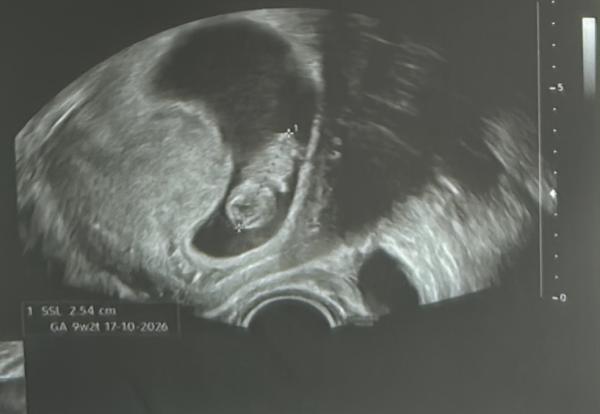

Hallo zusammen 🙋🏼‍♀️ bin zwar erst in der 10. SSW, aber kennt sich jemand aus mit der Ramzi und nub Methode aus ? Erkennt ihr was auf den US-Bilder ? Liebe Grüße  Anja